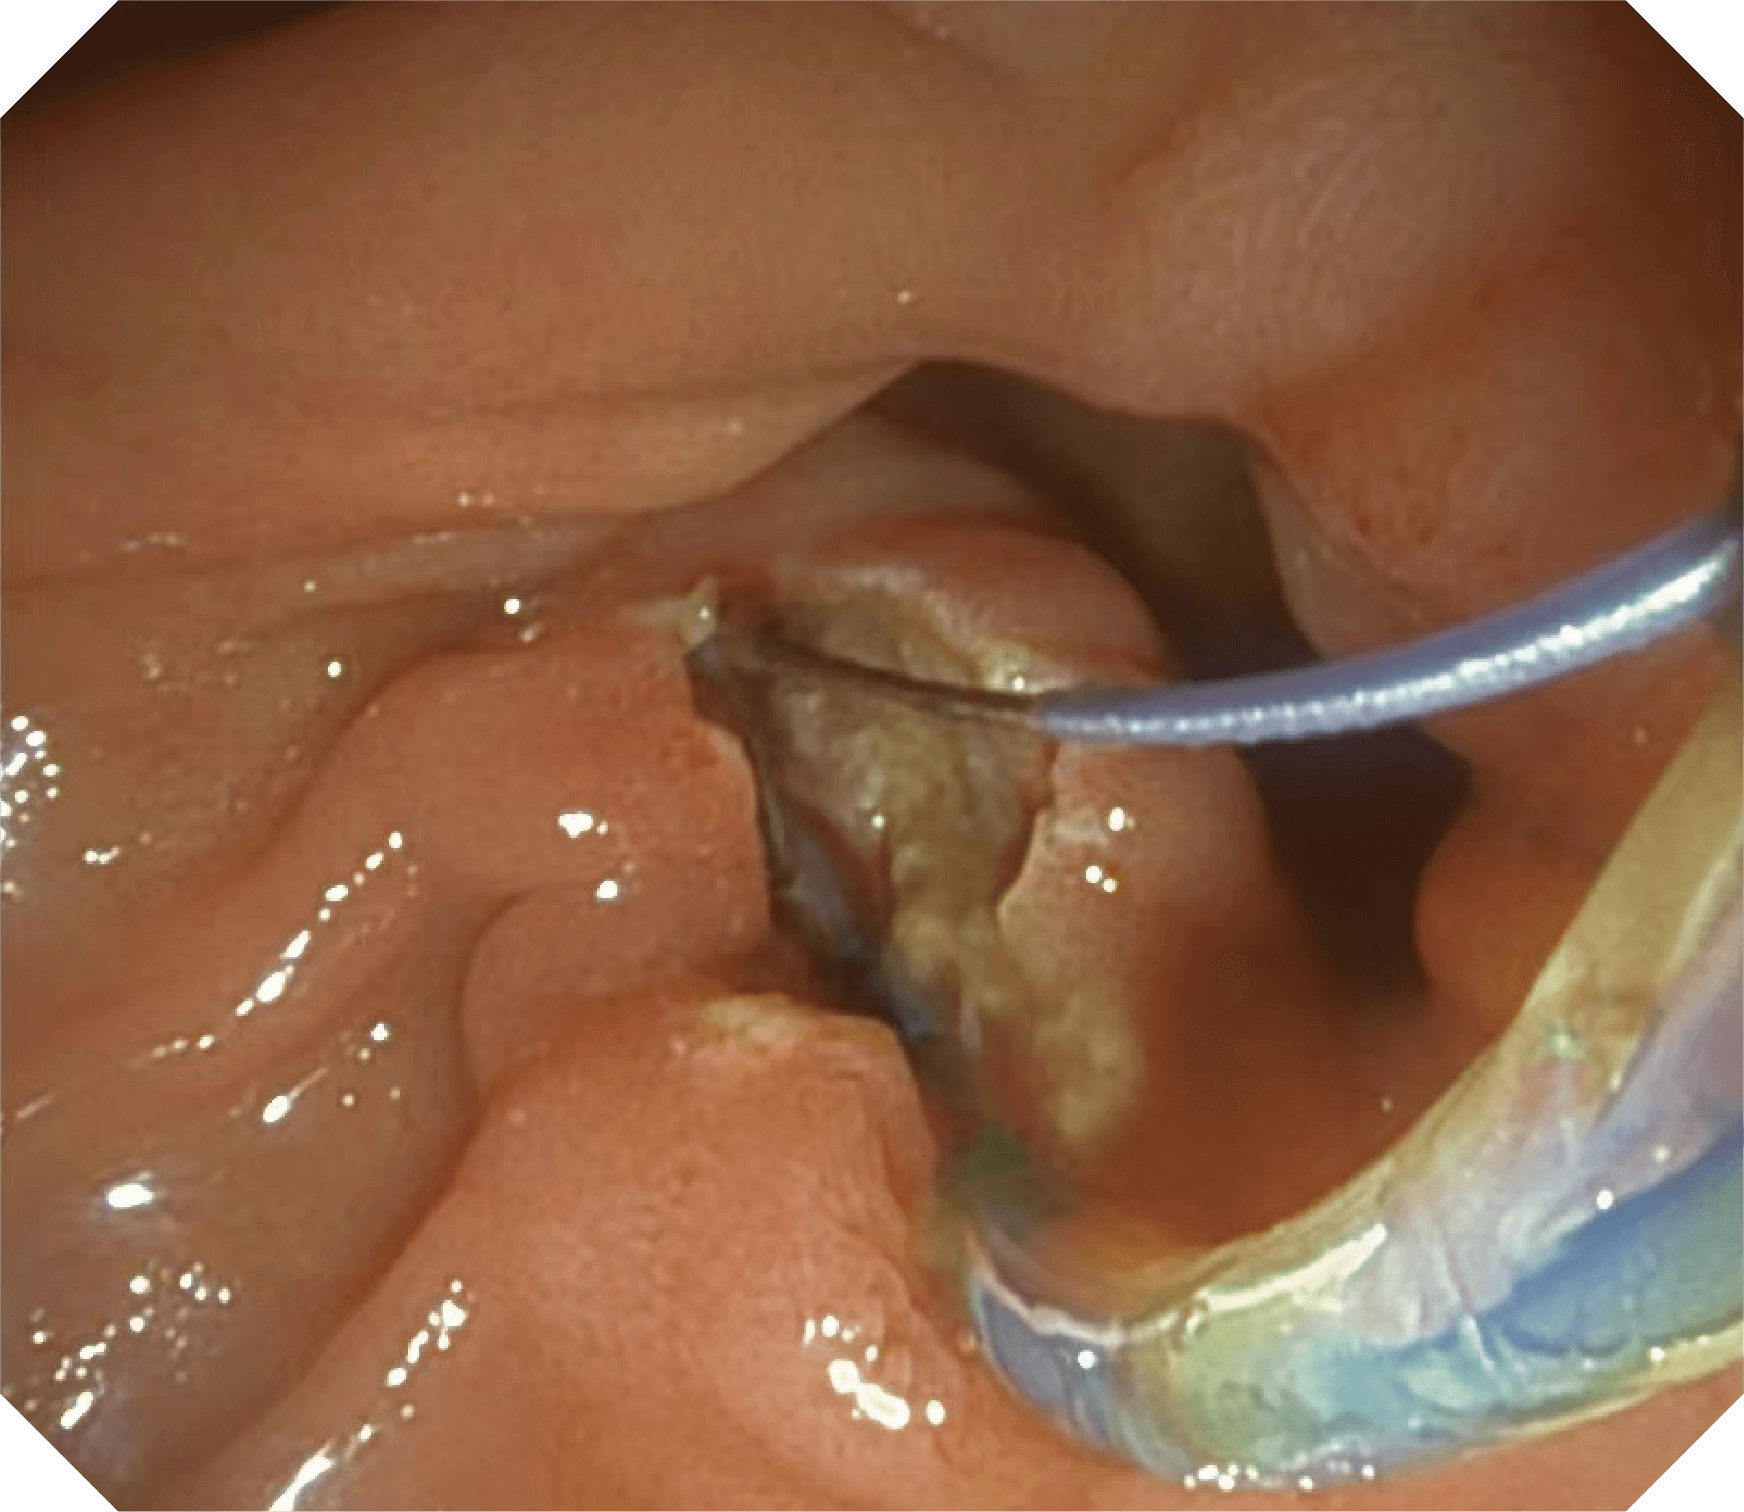

4.2mm大鉗道,器械交換更順暢

導(dǎo)絲機(jī)械鎖緊功能

V槽設(shè)計(jì)提升導(dǎo)絲控制

當(dāng)切開刀伸出視野外時(shí),導(dǎo)向面引導(dǎo)其回歸視野